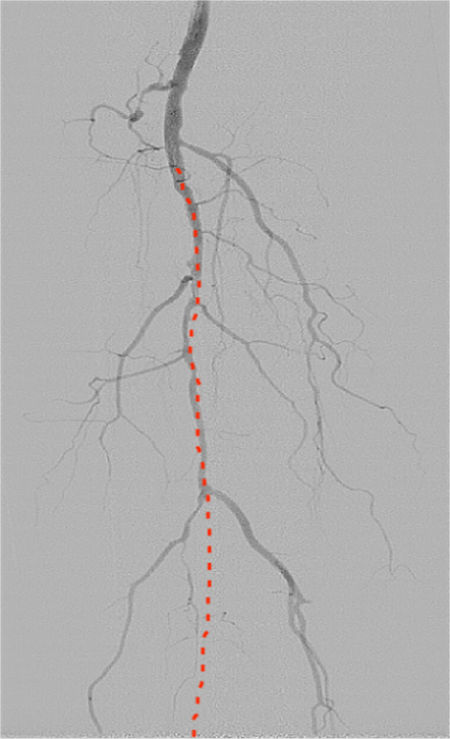

此次手術(shù)針對患者的下肢動脈粥樣硬化閉塞癥和糖尿病足周圍血管病變,預(yù)開通血管,使因血運不足引起的潰瘍愈合。(紅色虛線標(biāo)注為狹窄閉塞的血管)

團(tuán)隊?wèi){借精準(zhǔn)的術(shù)前評估、規(guī)范的手術(shù)操作,成功為患者開通直達(dá)創(chuàng)面血管,改善創(chuàng)面供血。